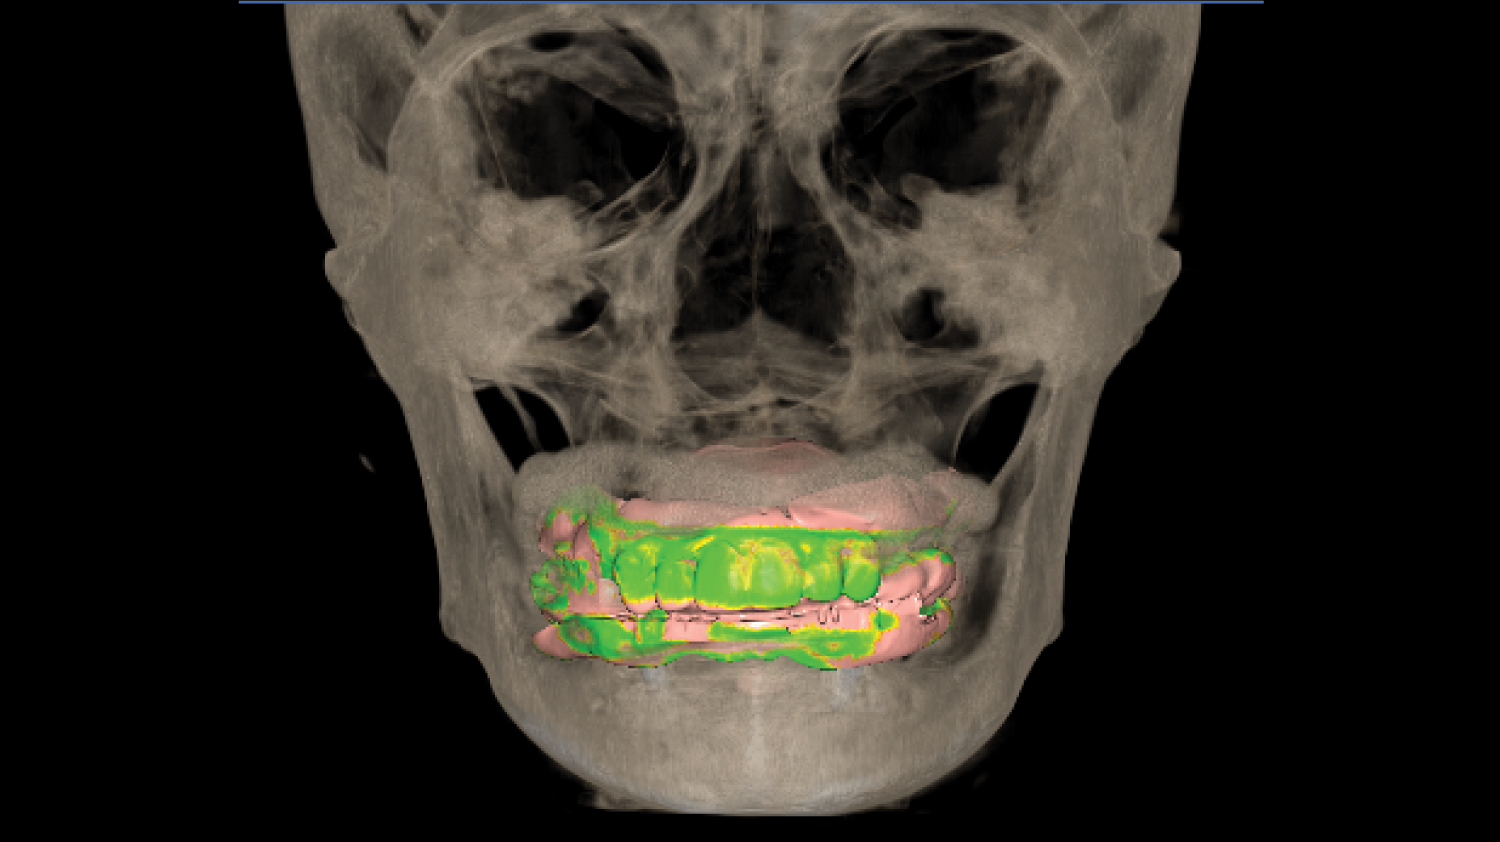

Director’s Clinical Cases

Director’s Clinical Cases